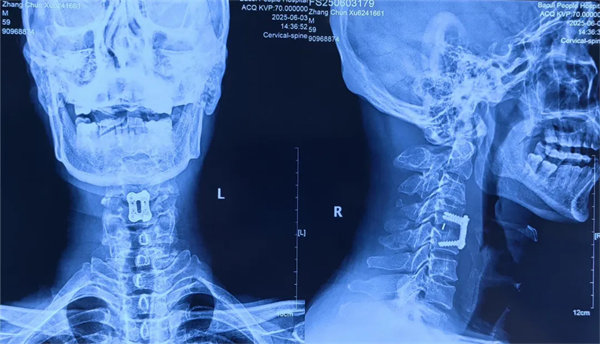

患者受傷后曾在外院接受保守治療,但肢體麻木癥狀持續(xù)存在。轉入我院時,頸椎CT及MRI顯示:頸4/5椎骨折脫位,脊髓受壓明顯,若不手術治療,可能面臨永久性神經功能障礙。我院骨四科團隊,制定了前路ACDF手術方案:通過頸前側入路,切開復位、切除椎間盤,解除脊髓壓迫,同時植入融合器、鈦板固定,重建頸椎正常序列及穩(wěn)定性。術后患者麻木感消失,復查顯示頸椎序列恢復良好,目前已康復出院。

術后